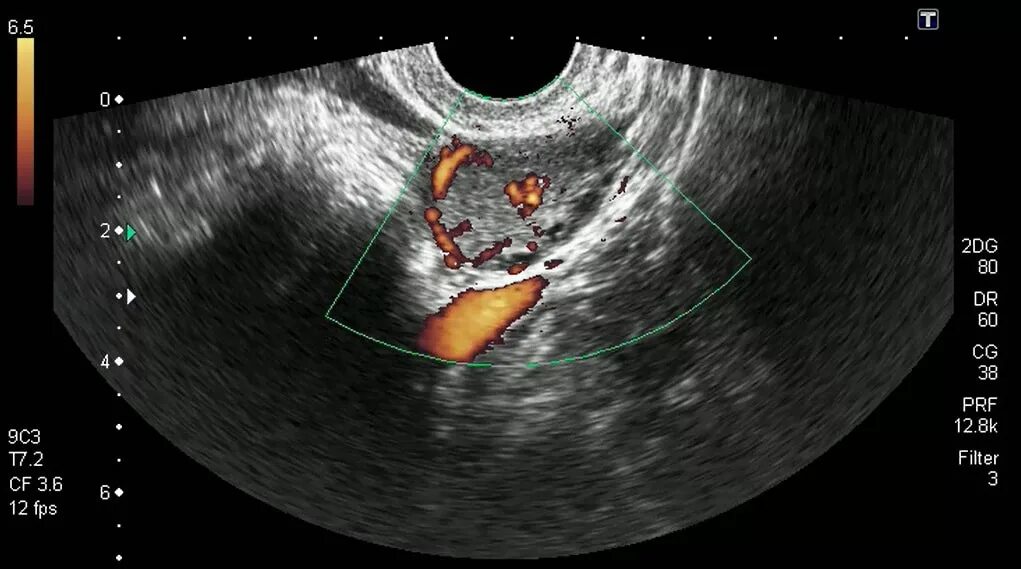

Фолликул после овуляции